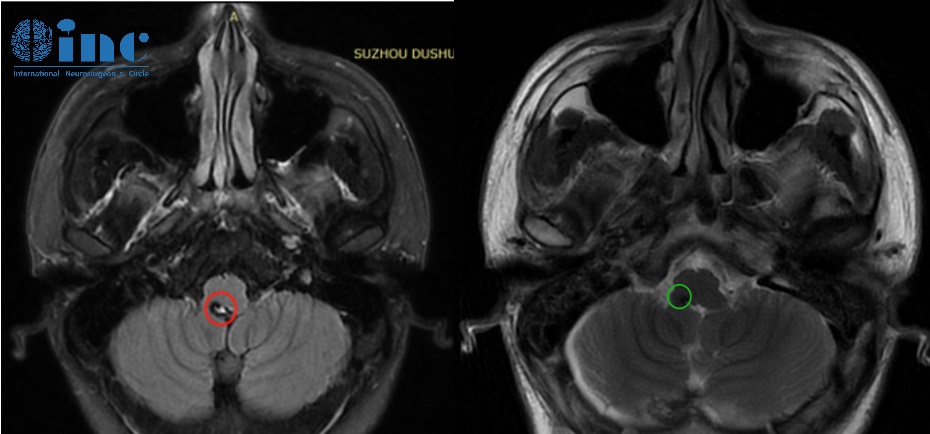

21岁男孩-脑干海绵状血管瘤

简要病史:21岁的大男孩阿豪2年前在学校他却突然感觉站不稳想吐,之后持续数日的头晕、乏力、睡眠质量下降呕吐,让阿豪警惕起来,观察后不见好转的他来到医院进行检查,没想到检查结果果然异常,头部CT显示延髓后方近小脑见大小约6.8*9.9mm的片状高密度阴影,怀疑脑干海绵状血管瘤。面对面直接线下咨询巴教授,巴教授表示脑干海绵状血管瘤需要手术,自己可以全切。

治疗过程:3月29日,在苏州独墅湖医院,巴教授顺利为阿豪全切脑干海绵状血管瘤。

术后情况:术后1天巴教授ICU查房,阿豪意识清醒、对答如流,吞咽、舌头活动、头部活动等情况,术后9天,阿豪恢复良好,行走自如。术后两周,阿豪恢复很好,无新发症状,阿豪现在已经顺利出院。术后两个月恢复正常生活。